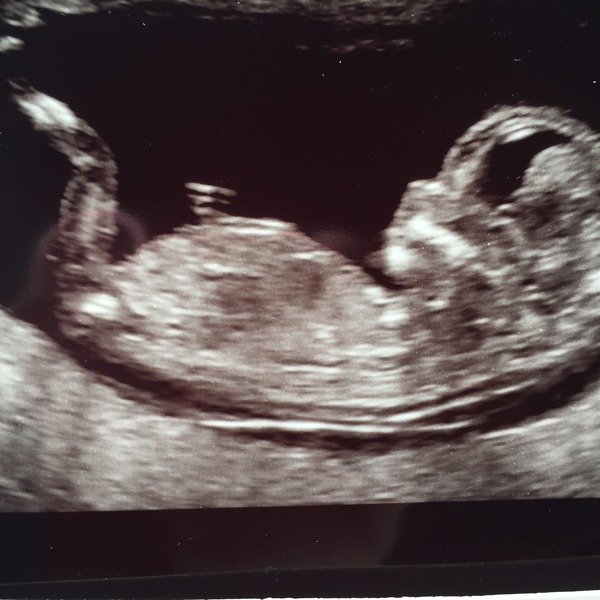

Hi guys, lots of lovely scan pics on here today! Scan went well today, saw a lovely wiggly baby. Saw lovely images of the baby but pics aren't great, I've attached one anyway. Measurements were fine for NT, so fx all will be well. Happy days.

August 2016 (3) - scans fast approaching, teeny tiny bumps appearing, and sickness easing....we hope!